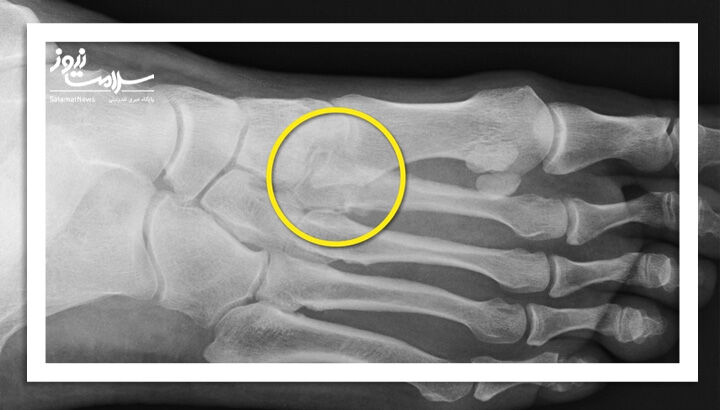

شکستگی استخوان

پای انسان از استخوانهای کوچکی تشکیل شده که به راحتی میتوانند بر اثر ضربه یا سقوط بشکنند. برای درمان شکستگی، پزشک معمولاً با روش های خاص استخوان را در جای خود ثابت نگه میدارد.